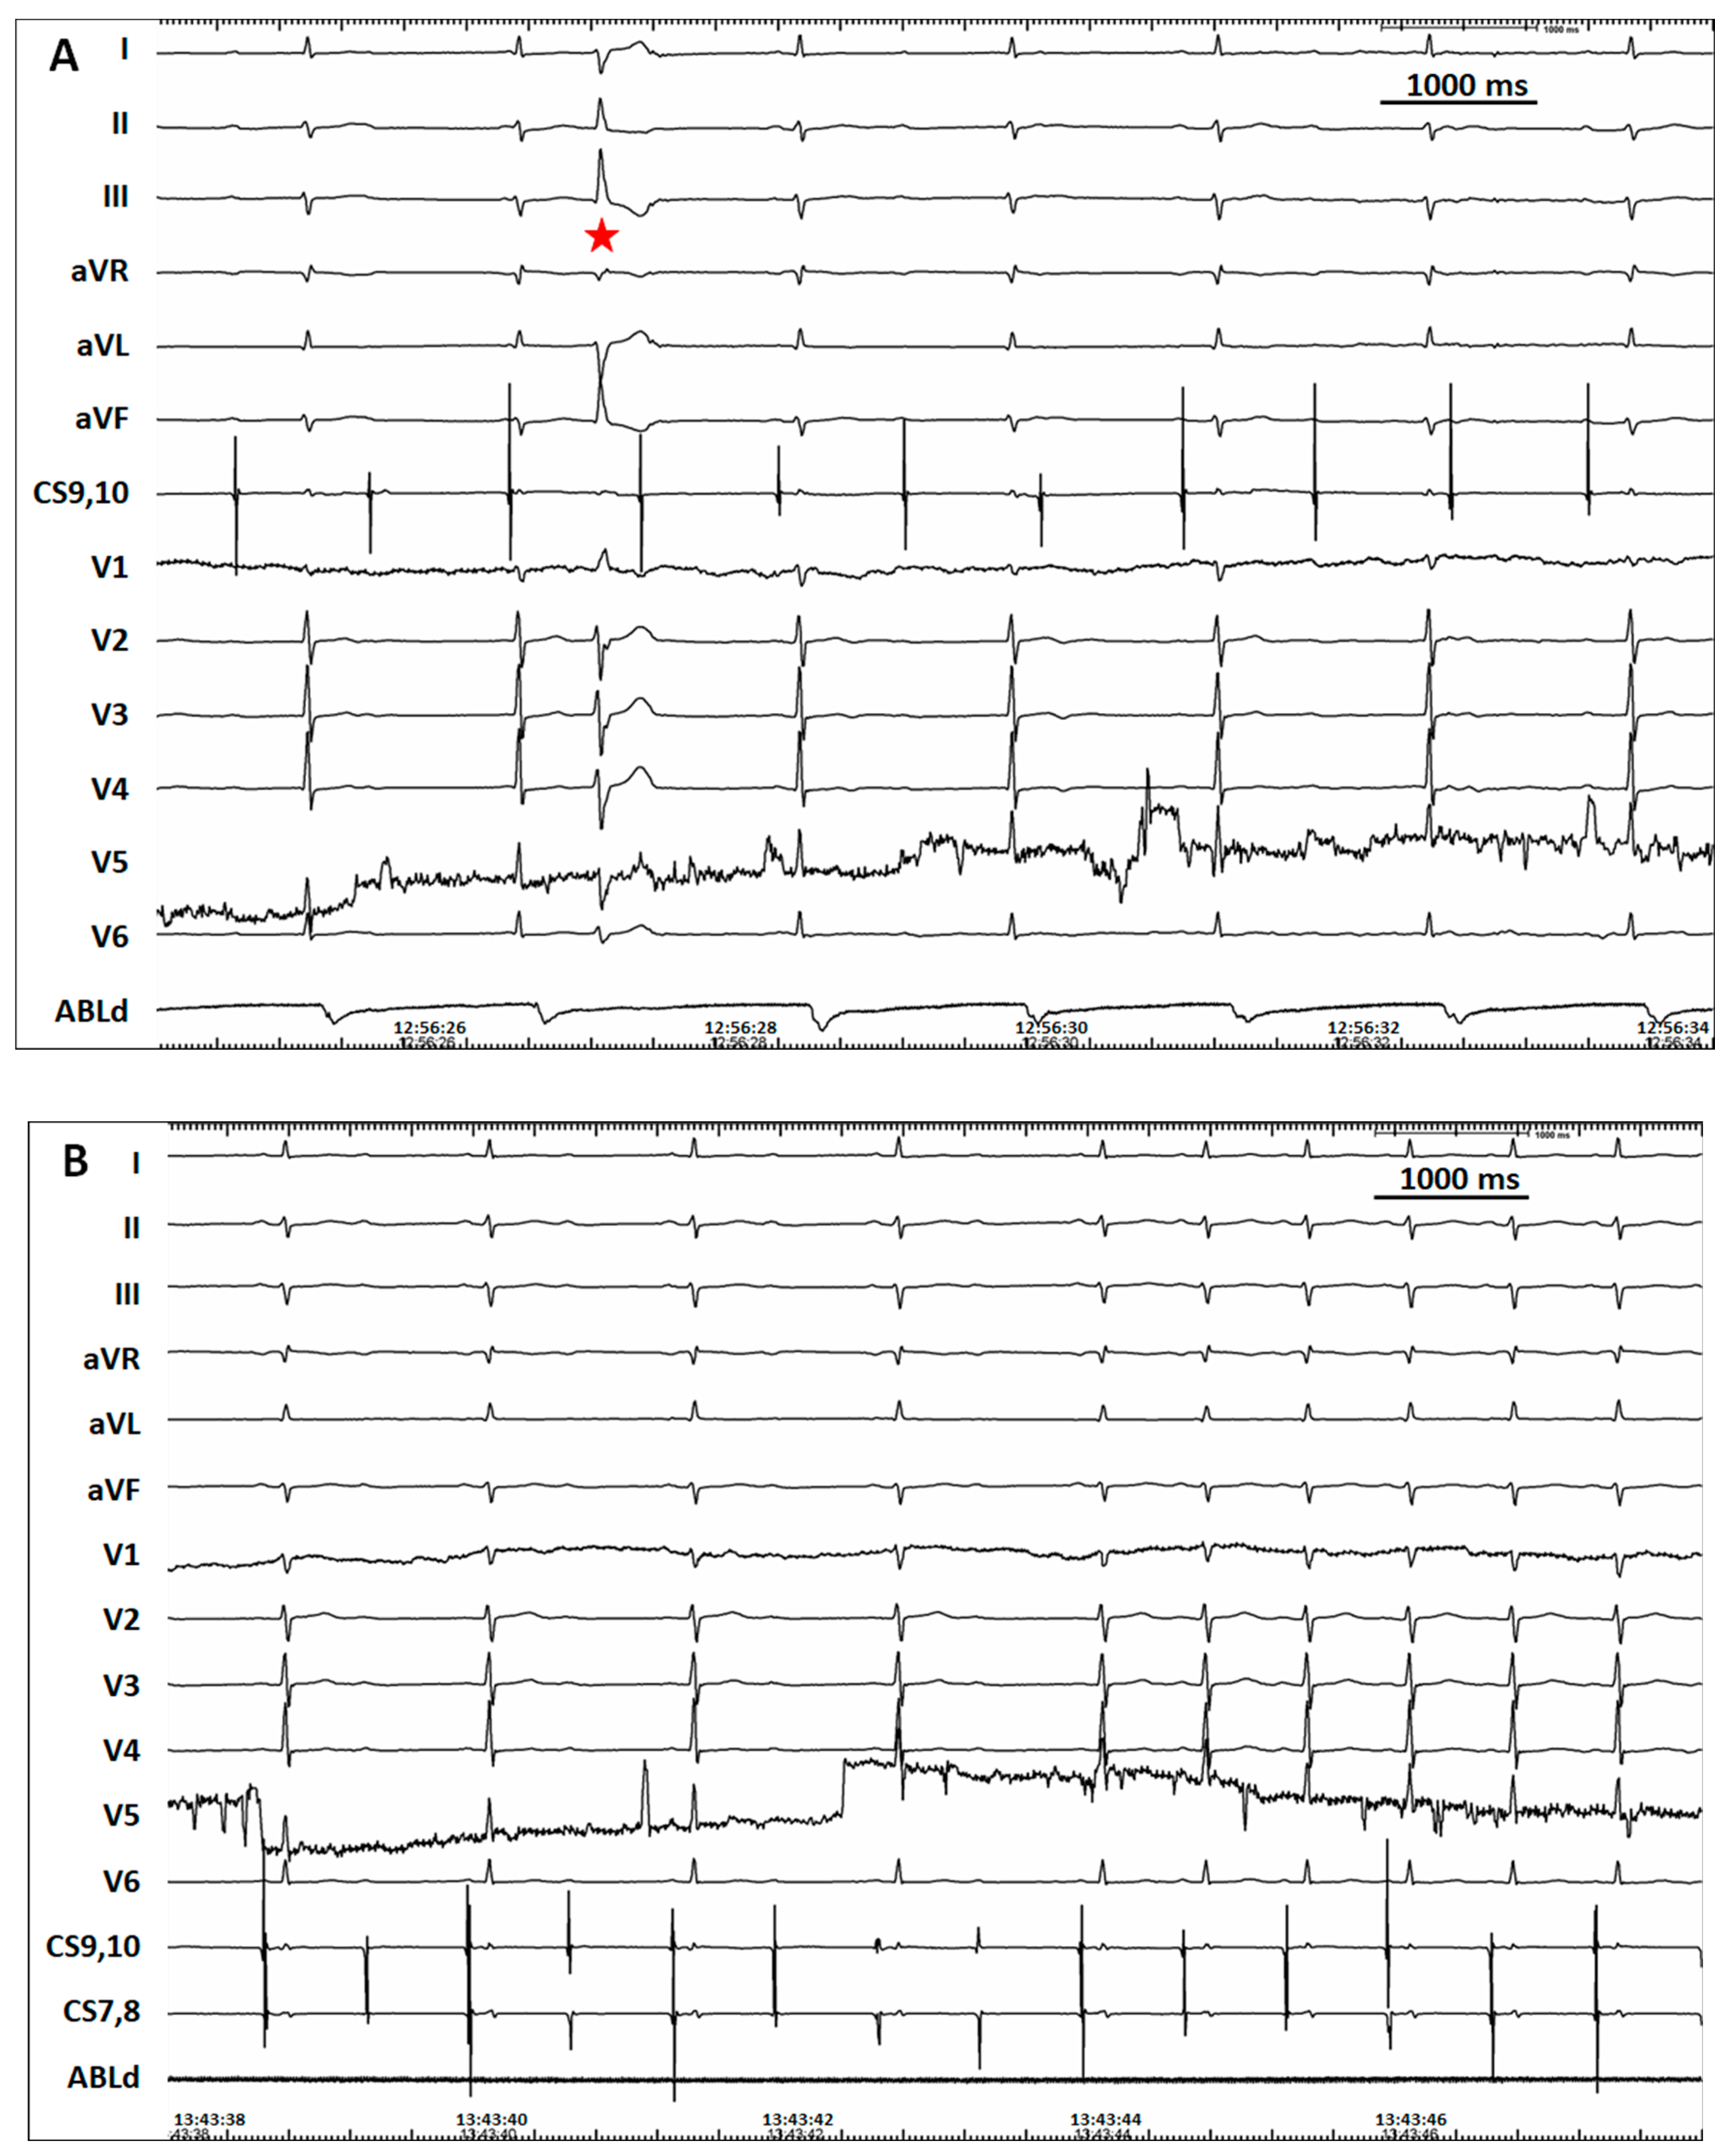

2. Case Report